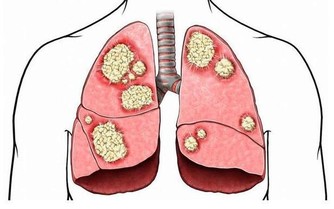

沒有屁放:疾病信號如果長時間不放屁,說明問題嚴重。新生兒不放屁,要檢查是否為無肛症或肛門發育不全。大人沒有屁放,腹部發脹如鼓,說明腹部脹氣,這就要考慮肛門直腸是否有毛病,如炎症、腫瘤、便秘、痔瘡等,必要時需肛門插管排氣。患有腸套疊、腸扭轉、腸梗阻無屁,是因為屁被腸子堵住。

▲如果無屁放出並伴有劇烈的腸絞痛者,必須緊急到醫院求治,作為急診進行搶救處理。此外,胃穿孔、闌尾炎穿孔形成的腹膜炎,腹部發硬,觸之劇痛,也可無屁。